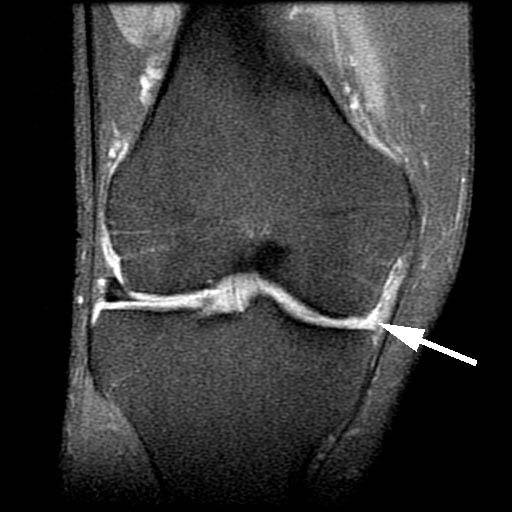

3.A coronal MRI image demonstrates the complete absence of the posteromedial aspect of the medial meniscus.

4.Meniscal allograft transplantation was recommended to the patient based on the overall healthy appearance of his articular cartilage, the normal alignment of the lower extremity, and the near complete absence of the posterior horn of the medial meniscus. In the image at the top of the series of 3 above, the meniscus tissue is shown to be completely absent (black arrow) from the edge (capsule) of the joint. In the image in the center, the allograft meniscus is shown at the time of surgery. On the image at the bottom of the series of 3 above, the post-transplantation images of the graft are shown (black arrow)